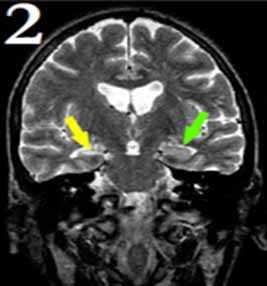

В правой височной доле (области гиппокампа и парагиппокампальной извилины) определяется зона повышения интенсивности МР-сигнала по Т2 без четких контуров. Отмечается асимметричное нерезкое расширение височного рога правого бокового желудочка.

2. Изменение структуры гиппокампа и интенсивности сигнала от его элементов.

Желтая стрелка показывает пораженную область гиппокампа. Видно, что эта область меньше, по сравнению со здоровой стороной (зеленая стрелка).

Признаки склероза могут сочетаться или присутствовать во всех отделах гиппокампа или в отдельных его элементах.

3. МР-картина очагового глиоза левого гиппокампа.

4. Полярная субатрофия левой височной доли.

Признаки парциальной эпилепсии. По данным предыдущего РКТ исследования - признаки кисты левой височной доли.

5. МР-картина узловой субкортикальной гетеротопии левой лобно-теменной области.

В первом случае визуализируются узлы гетеротопии в субкортикальных отделах белого вещества парасагиттальных отделов левой лобно-теменной области.

На втором скане - единичный мелкий узел гетеротопии в белом веществе правой лобной доли (характеристики МР-сигнала идентичны серому веществу головного мозга)

На третьем изображении - множественные узлы гетеротопии вдоль стенок переднего рога левого бокового желудочка и задних рогов обоих желудочков (характеристики МР-сигнала узлов идентичны серому веществу головного мозга)